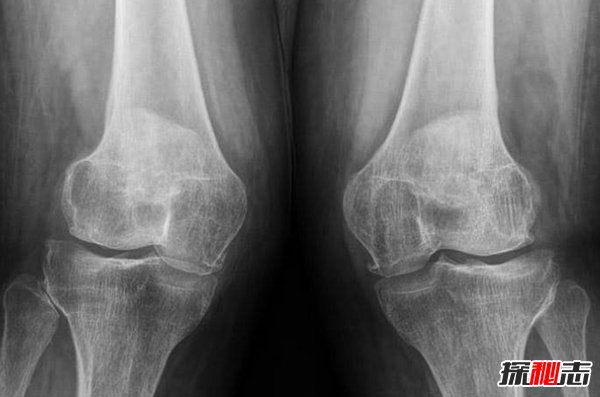

9、膝蓋恐懼癥

史上最不可思議的十大恐懼癥 沒(méi)有人能接受的了(震驚)

這是一個(gè)嚴重的問(wèn)題,根據專(zhuān)家的說(shuō)法,它可能源于先前的傷害,也可能是宗教的影響,因為某些信仰禁止膝蓋被看到,強迫你跪下祈禱,乞求寬恕。